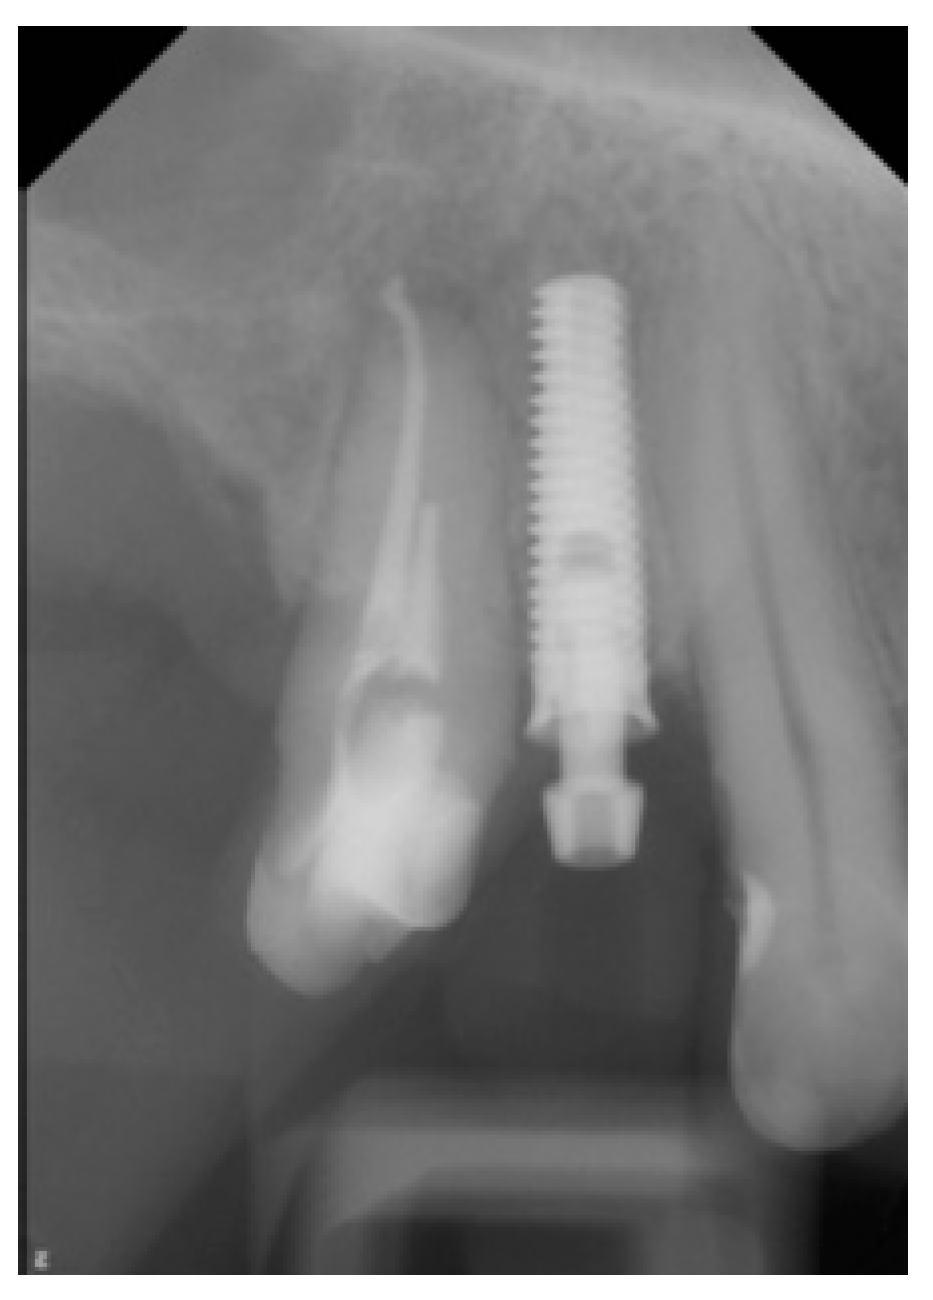

| Implant type | Tissue-Level (Matrix, TRI Swiss Implants) |

| Implant diameter platform | 3.7 mm |

| Implant diameter enossal | 3.3 mm |

| Implant length | 11.5 mm |

| Surgical | Computer-assisted implant surgery |